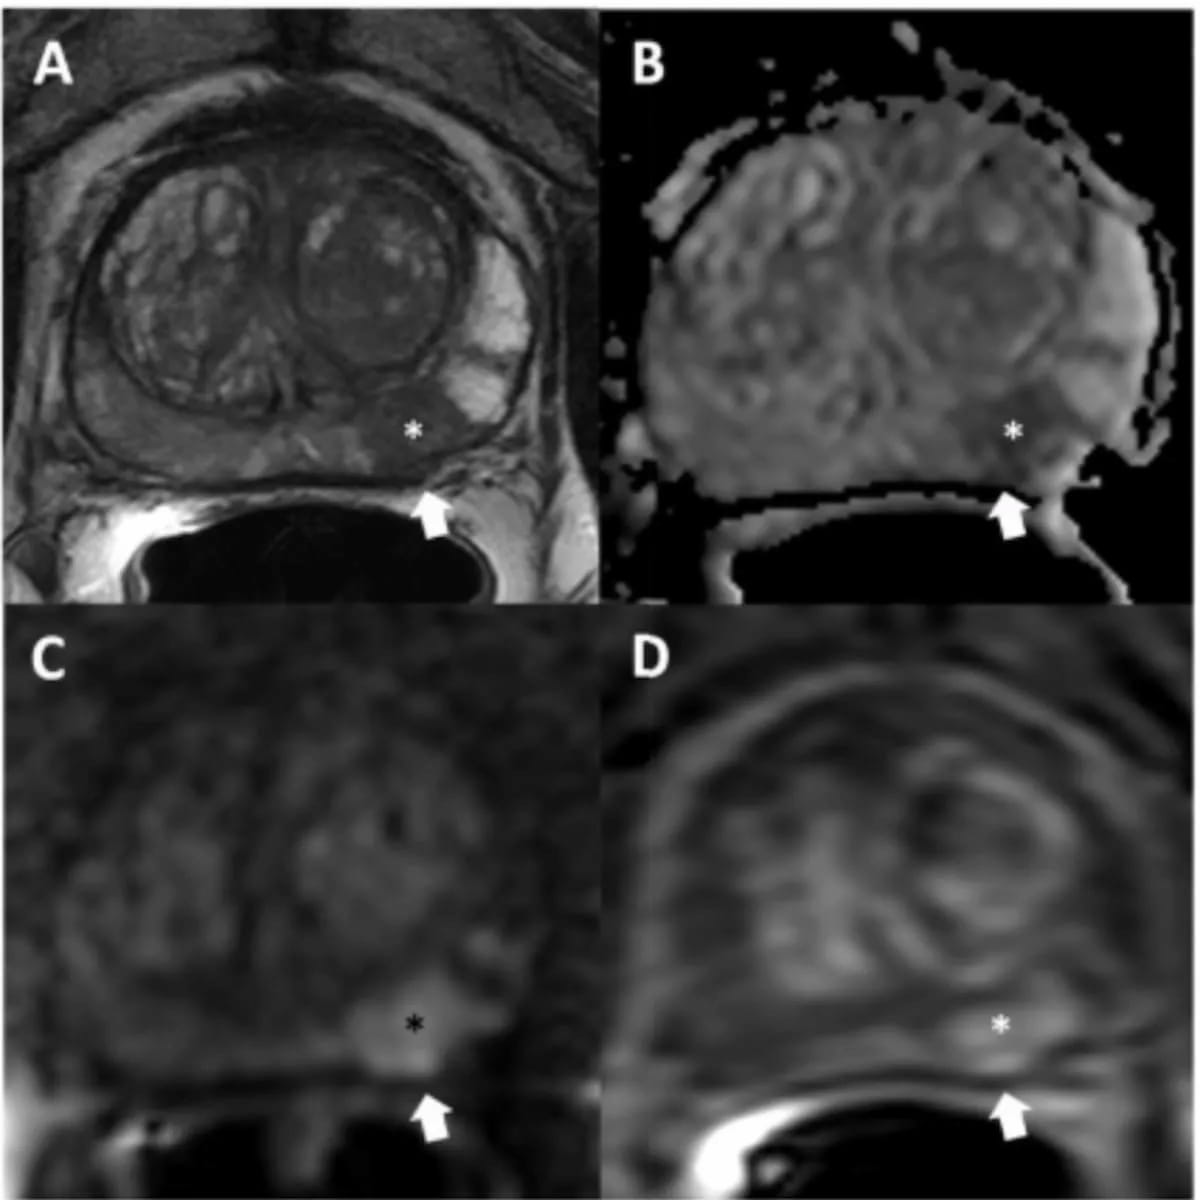

A model that combines multiparametric MRI findings with clinical factors may enhance the accuracy of predicting clinically significant prostate cancer and significantly reduce unnecessary systematic prostate biopsies in biopsy-naïve patients.